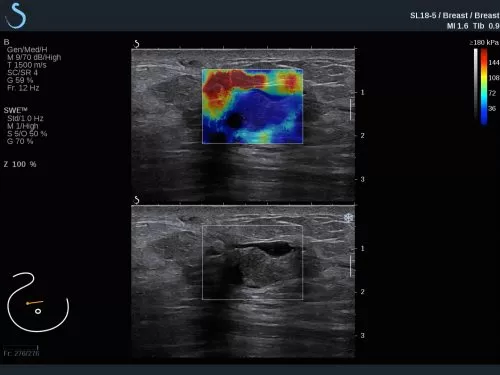

The Aixplorer Ultimate ultrasound unique capabilities of Shearwave Elastography, are going to be presented in the workshop which will be held on 29/9/2018, during the ultrasound – elastography workshop.

Find out how SWE can help you increase the sensitivity of the ultrasound exam, the biopsy predictive value, and how a DCIS can be upgraded to IDC.